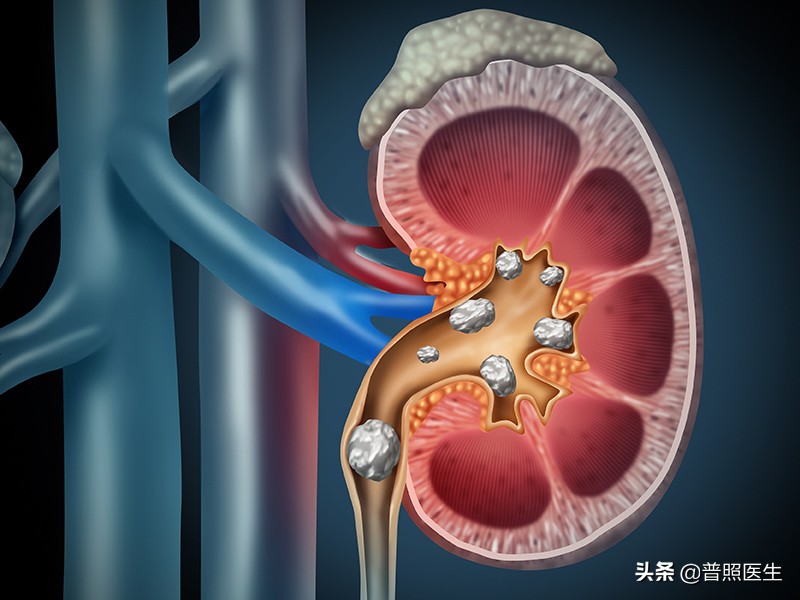

上尿路结石:输尿管被结石卡压,会导致尿路平滑肌剧烈痉挛,引起剧烈腹痛腰痛,结石划伤尿路粘膜引起血尿。肾里面的结石基本上不会产生疼痛,所以很多人有肾结石好多年了,也是到了体检时才发现自己有泌尿系结石。